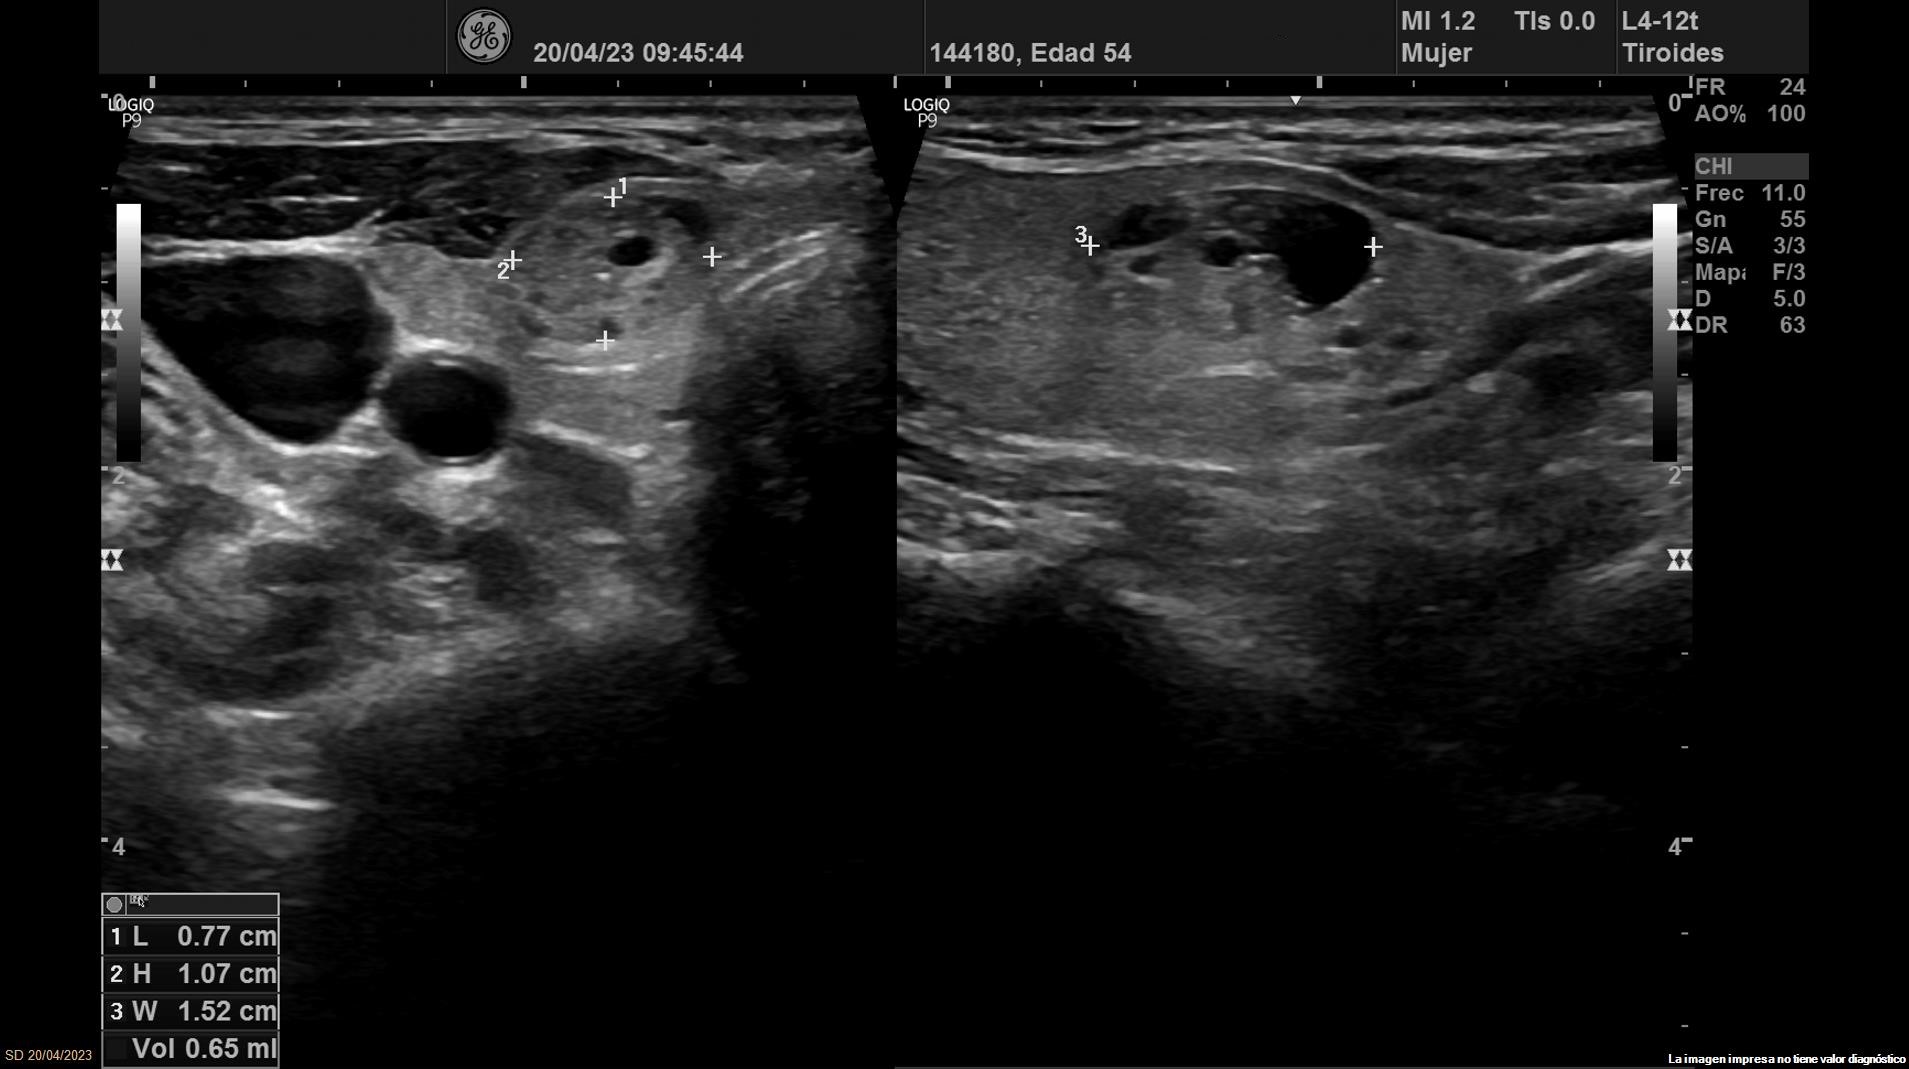

• Lóbulo tiroideo izquierdo: tamaño normal. En la mitad inferior se objetiva un nódulo de 11 x 14 x 20 mm (Vol 1,52 ml), bien definido, sólido e iso/hiperecoico, con halo fino hipoecoico, sin calcio y con vascularización de predominio periférico (ATA: baja sospecha).